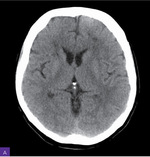

Rycina 1A, B. Tomografia komputerowa mózgu. Widoczne nasilone, rozsiane ogniska istoty białej głębokiej obu płatów czołowych o charakterze naczyniopochodnym, znacznie słabiej wyrażone zmiany o podobnym charakterze okołokomorowo i w lewej torebce zewnętrznej

Tomografia komputerowa (TK) głowy wykazała na pograniczu zakrętu czołowego górnego i przedśrodkowego lewej półkuli mózgu niewielki obszar ostrego zawału z unaczynienia gałęzi przeszywających powierzchownych lewej tętnicy środkowej mózgu. W porównaniu z poprzednim badaniem obrazowym głowy pojawiły się nasilone rozsiane ogniska istoty białej głębokiej obu płatów czołowych o charakterze naczyniopochodnym, znacznie słabiej wyrażone zmiany o podobnym charakterze okołokomorowo i w lewej torebce zewnętrznej (ryc. 1).